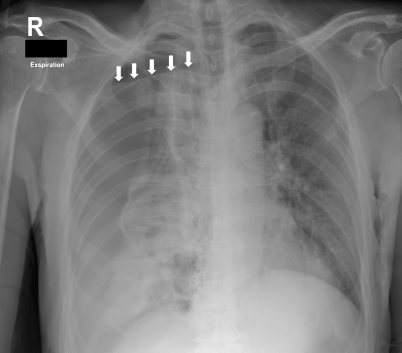

Da sich die Schocksymptomatik des Patienten verschlechterte und er einen abrupten Sauerstoffsättigungsabfall erlitt, erfolgte die notfallmäßige Punktion des rechten Hemithorax mittels einer großlumigen Kanüle (14 Gauge) mit anschließender Platzierung einer Thoraxsaugdrainage. Dadurch besserte sich die hämodynamische Instabilität des Patienten. Über die Thoraxsaugdrainage entleerten sich mehrere Liter purulenter Flüssigkeit, welche mikrobiologisch untersucht wurde. Eine im Anschluss durchgeführte Computertomographie des Thorax konnte einen Lungenabszess sowie den verbliebenen Pneumothorax nachweisen (Abb. 2). In den Pleurakulturen wurden Staphylococcus aureus, Streptococcus constellatus und Prevotella spp. nachgewiesen, die auch in den histologischen Proben der damaligen transbronchialen Biopsie nachweisbar waren.

Abb. 2

Computertomographie des Thorax (transversal) nach Platzieren der Thoraxdrainage: Konsolidierung des rechten, unteren Lungenlappens, welche einem Lungenabszess entspricht, sowie residualer Pneumothorax (rote Pfeile)